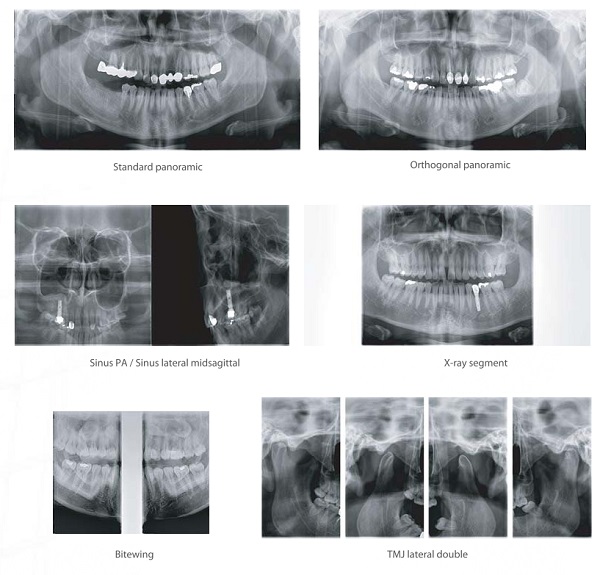

With various scan modes of Panoramic, CT and Cephalometric*, assist in accurate diagnosis.